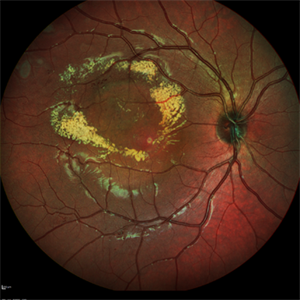

Coats Disease

Dec 9 2021 by Filip Kecer

Multi-color image of a 14-year-old boy with Coats disease.

Photographer: Filip Kecer, National Institute of Childrens Diseases

Imaging device: Spectralis, Heidelberg Engineering

Condition/keywords: Coats' disease